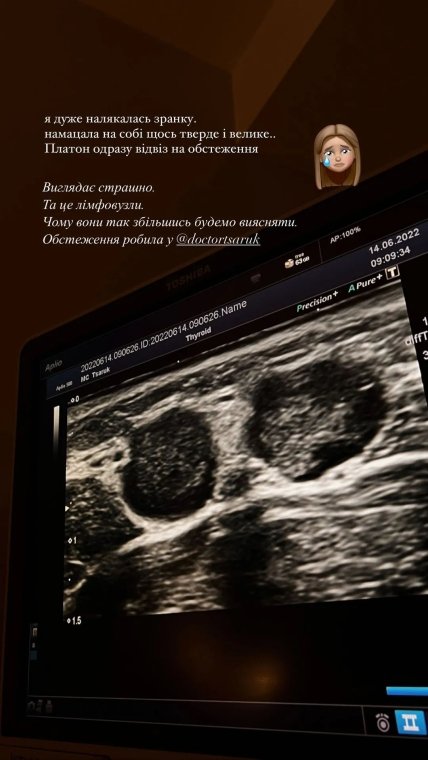

Во вторник утром, 14 июня, девушка сообщила в сторис Инстаграм, что "нащупала на себе что-то твердое и большое". Как призналась Александра, она очень испугалась.

"Платон сразу отвез на обследование. Выглядит страшно. Это лимфоузлы. Почему они так увеличились, будем выяснять", — написала Саша Бо.